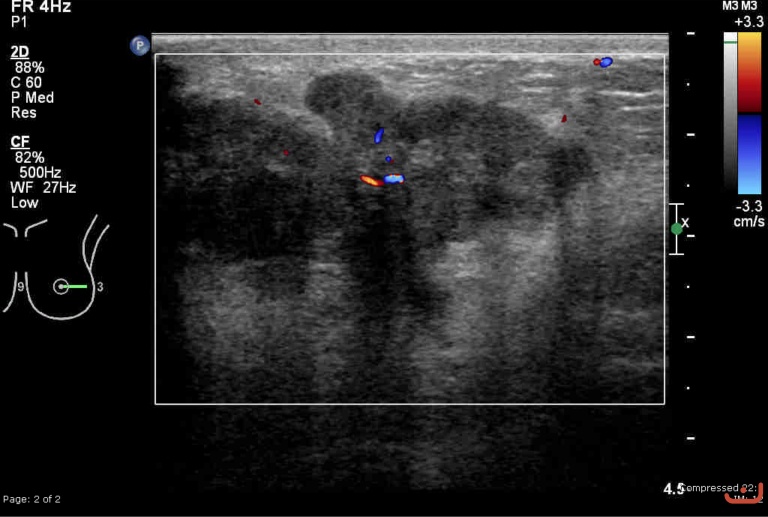

Malignant solid mass

Friday, 22 May 2015